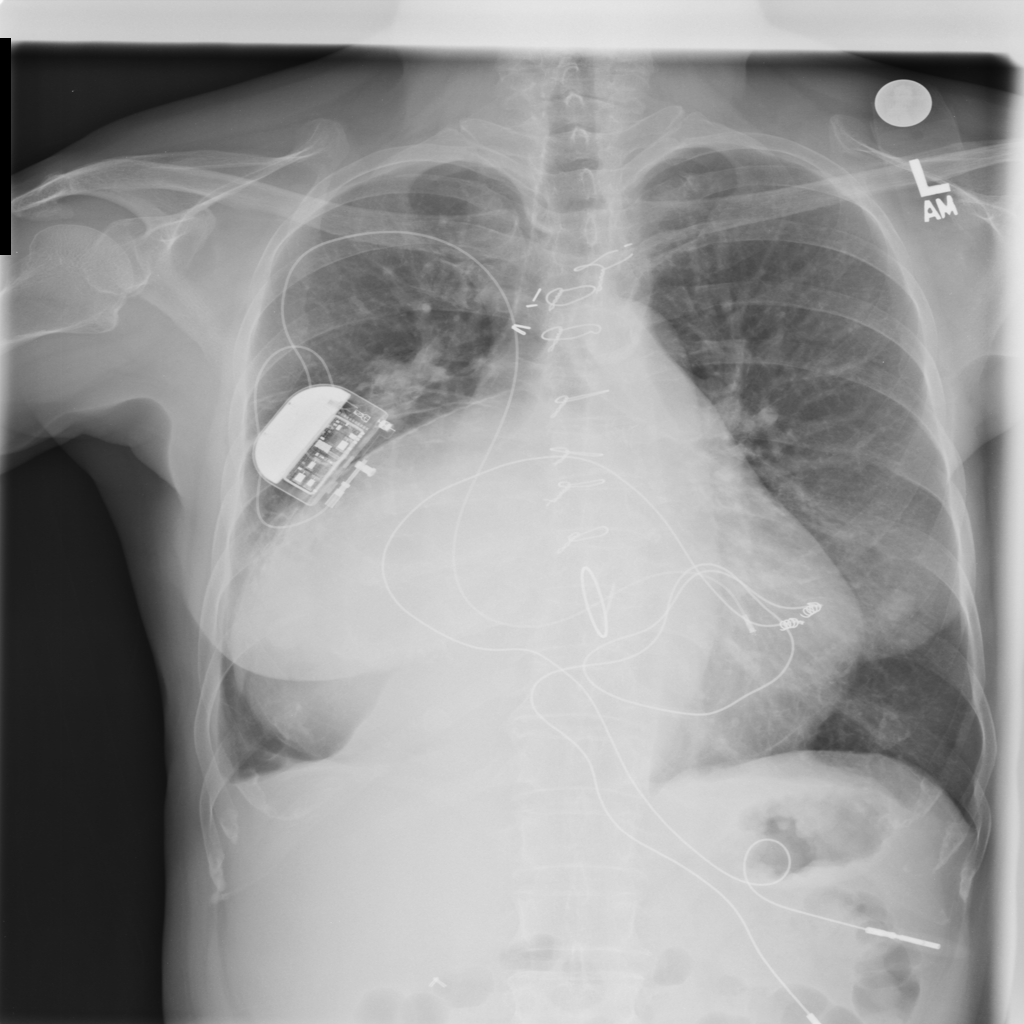

Cardiomegaly

Cardiomegaly means the heart appears enlarged on the chest X-ray. It is a descriptive imaging finding that can be related to heart strain, chronic pressure or volume changes, or even projection effects.

Support Devices

Support devices on chest X-ray include lines, tubes, and implanted hardware whose position may affect safety and management.

Showing up to 90 reference images for Cardiomegaly.

PAT-4639 · IMG-045Cardiomegaly

PAT-4639 · IMG-045

PA